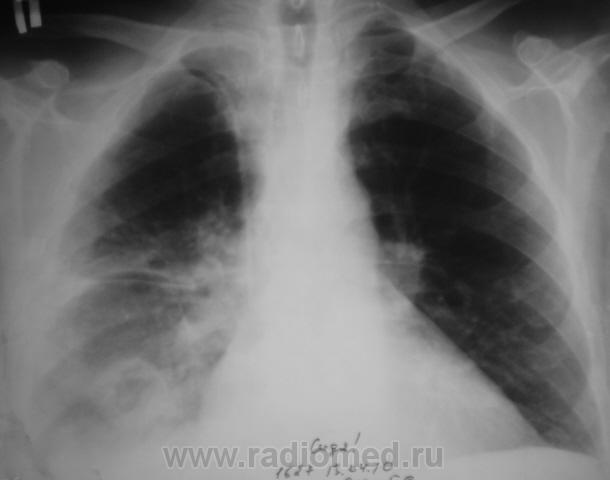

Пациенту в "области" была произведена операция по поводу "аденомы" предстательной железы. Через 3 дня после операции состояние пациента резко ущудшилось, была назначена рентгенография. Снимок ниже.

Валентин Львович! Наверняка перед операцией пациенту выполнялась ФЛГ и там возрастная норма (надеюсь, что это так). Следовательно "аденома" не является причиной изменений в легких. Тогда остается холодная операционная и абсцедирующая пневмония правого легкого.

Но все таки абсцедирующая пневмония!

Объясните мне, не специалисту в пульмонологии, может ли абсцесс сформироваться за 3 дня. Или я что-то не так поняла? Видна дренированная полость, округлая, довольно четко отграниченная. В плевральной полости жидкость.

Уважаемая Nela! Двайте пойдем "логическим путем"(надеюсь, что вместе). Пожилой пациент готовится к плановой операции (аденомэктомии). Насколько мы знаем организацию нашего здравоохранения, перед плановой операцией пациент в амбулаторном порядке проходит кучу предоперационых исследований (анализы крови, мочи, ЭКГ, УЗИ простаты, почек, ФЛГ и т.д.). Если все в порядке и противопоказаний к оперативному вмешательству не имеется, пациента берут на операцию. Если имеются малейшие отклонения - то до их устранения. Если противопоказания не устранимы - пациенту в плановой операции может быть отказано. Пациента на операцию взяли, т.е. все в порядке, в том числе и в легких. Через три дня после операции мы видим представленную рентгенологическую картину. Деструкция легочной ткани. Абсцедирующая пневмония, абсцесс легкого. Смею Вас заверить, по собственному опыту, и у пациентов зрелого возраста и у молодых пациентов в послеоперационном периоде (3-5 дней) возможно развитие осложнения послеоперационного периода в виде пневмоний, в том числе абсцедирующих. Причина - чаще всего внутрибольничный стафилококк. Операция - ослабление иммунитета- внутрибольничная (очень злая, доморощенная, устойчивая к антибиотикам) стафилококковая инфекция. Вот и  пришли к конечной точке нашего пути.

Но, так как пациент затяжелел...

Его выписали для долечивания "по месту жительства". На носилках был доставлен в рентген-кабинет. Решили произвести рентгенографию в ортоположении, дабы "усечь" уровень жидкости в "абсцессе", ну, да и сам "абсцесс..."